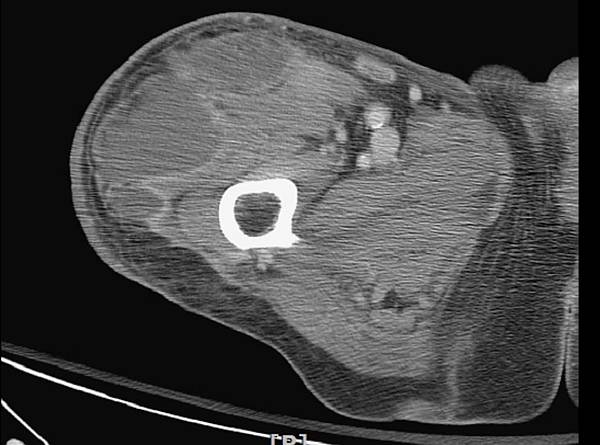

我請他們做電腦斷層看看吧!

果然是一個超大的病灶!!!

Morel-Lavallée lesion

一個高速撞擊或剪力作用下造成骨盆筋膜之上周圍出血的血塊封閉在皮下組織間.

更加證明MLL的確是一個筋膜上的病灶.